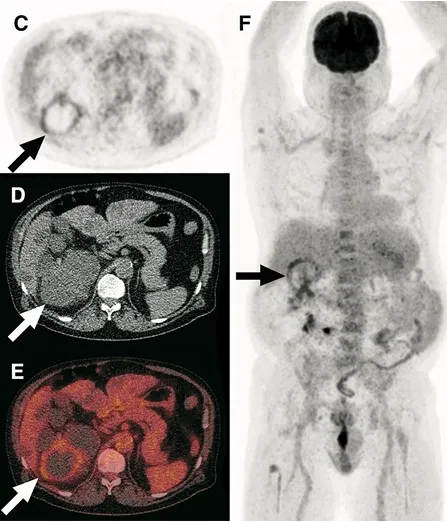

Finerenona e Empagliflozina: efeito na albuminúria é consistente mesmo em pacientes já em uso de GLP-1? O que o CONFIDENCE nos mostra